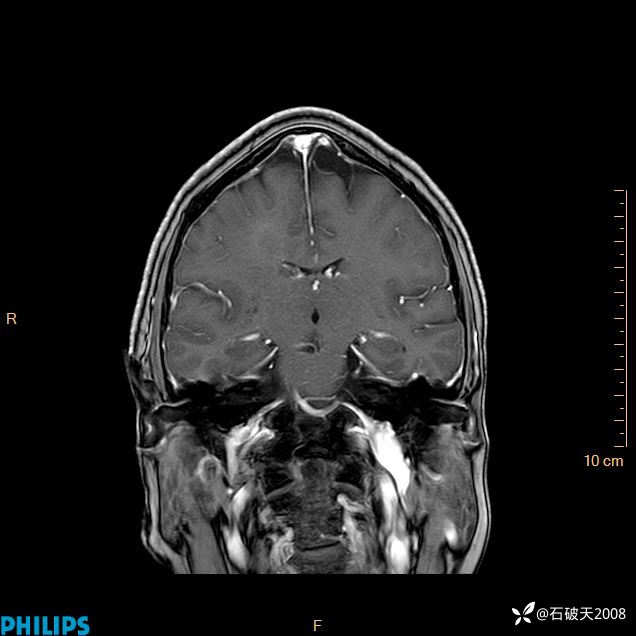

2024.2.21MR

增强冠状位